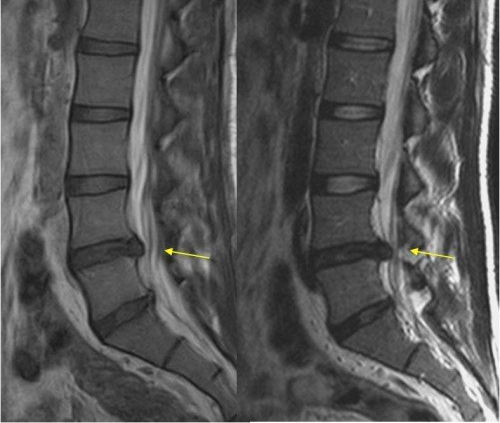

Comenzaremos explicando en qué consisten cada una de las pruebas diagnósticas, para qué están dirigidas y diferencias entre ellas: (sólo para los curiosos) La resonancia magnética utiliz a ondas de radio potentes y campos electromagnéticos para generar imágenes de tejidos internos, mediante cortes desde diferentes perspectivas. Se utiliza una frecuencia que no utiliza rayos X, por lo tanto, no genera una radiación al organismo. Se utiliza para cualquier parte del cuerpo, tanto para el aparato cardiovascular, pulmonar, digestivo, sistema nervioso central, etc. Pero nosotros hoy vamos a hablar desde la perspectiva musculoesquelética, ya que es nuestra especialidad. La radiografía genera rayos X, y se utiliza para ver estructuras óseas del cuerpo: la posición de hueso con hueso, articulaciones entre si, deformidad del hueso, rotura, fisuras, luxaciones... El cuerpo se expone a una pequeña dosis ionizante, por lo que esta prueba sí irradia, pero en proporciones que no son perjudiciales para nuestra salud, aunque no se recomienda realizar varias en cortos periodos de tiempo. La ecografía utiliza ondas sonoras de alta frecuencia, que junto con una pantalla y un cabezal (transductor) que capta la imagen, se observa in situ las estructuras que queremos valorar, ya sea en una embarazada el feto, o en el resto de personas el corazón, vasos sanguíneos, riñones, tendones, fibras musculares, etc. Estas dos últimas son las que con más frecuencia observamos en la clínica, que nos aporta información sobre inflamaciones de tejidos, roturas, o signos de degeneración. La electromiografía es una prueba invasiva, ya que se necesita para ello introducir una pequeña aguja que actúa como electrodo en el músculo a valorar. Registra la actividad nerviosa que existe en la zona cuando realiza un movimiento voluntario para ver la velocidad de respuesta y la calidad de la misma. Está dirigido para pérdidas de fuerza, hormigueos, pérdida de sensibilidad, todos los síntomas y signos que hagan sospechar de un problema del sistema nervioso periférico (tejido nervioso).